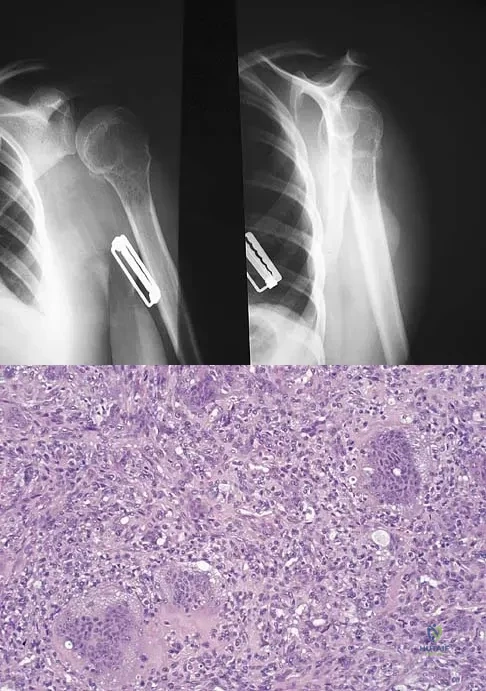

A 34-year-old woman reports constant midlateral arm pain after sustaining minimal trauma to the shoulder. Radiographs and a biopsy specimen are shown in Figures 29a and 29b. What is the most likely diagnosis?

Explanation